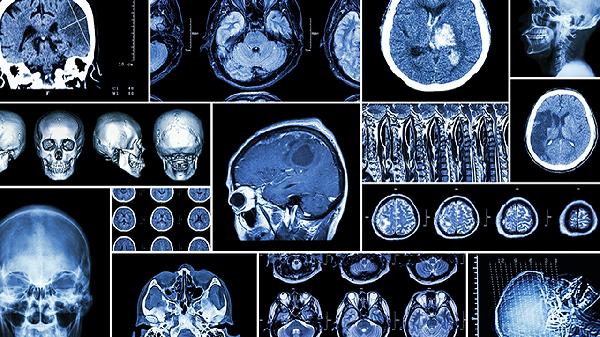

脑外伤颅骨缺损修补手术方法

脑外伤颅骨缺损修补手术方法主要有自体骨移植、钛网修补、三维钛板修补、聚醚醚酮修补及生物材料修补五种方式。